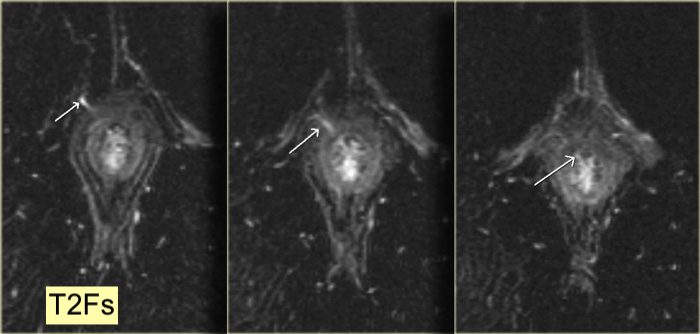

- Hyper T2/Flair (montre bien le trajet fistuleux)

Exemple: Fistule trans-sphincterienne à 6h

Exemple: Fistule trans-sphincterienne 11h